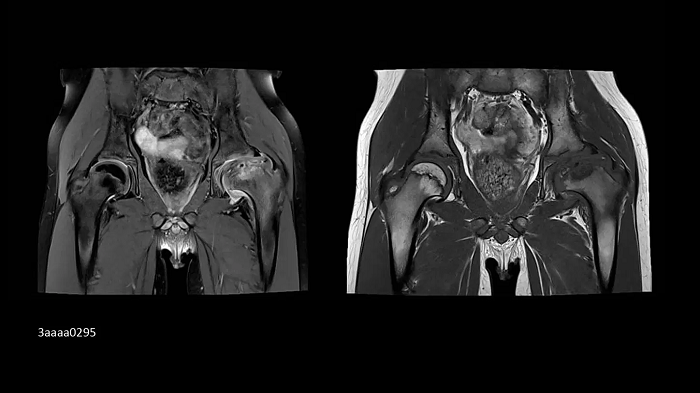

Orthopedics

Hip imaging with the new Ultraflex Coils

In pediatrics, high-resolution bilateral hip imaging with the new UltraFlex Coils was performed on an 8-year-old boy.

Image Credit: Radiologie Miinchen Harlaching, Munich, Germany